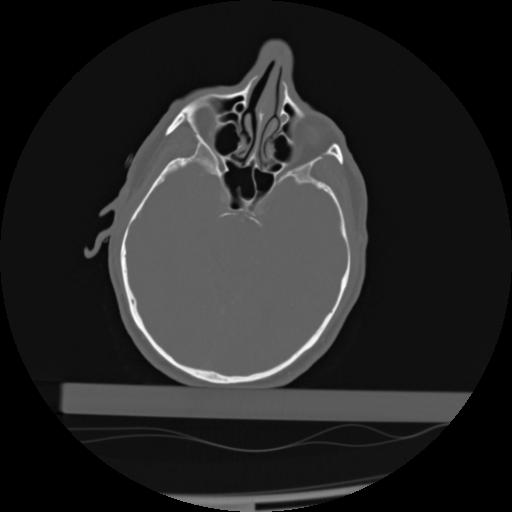

21 ANGIO,CE,Axial,3.0,ANGIO,,